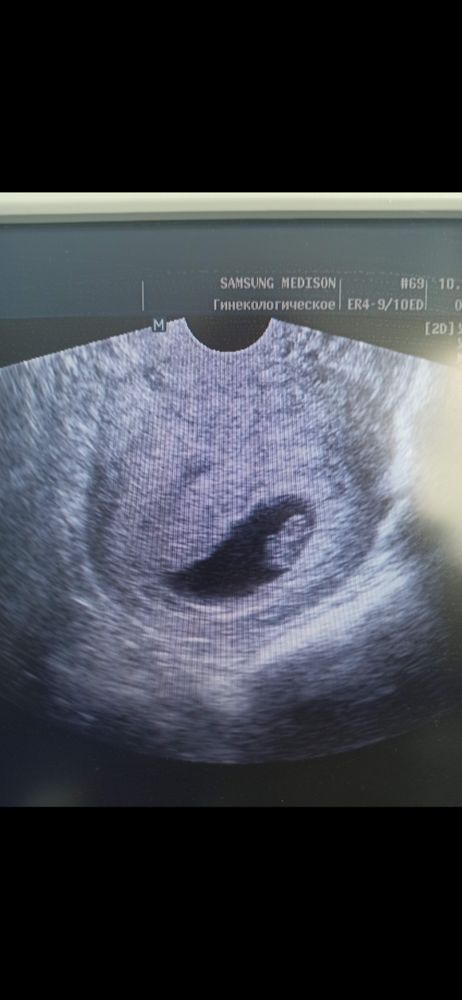

Изображение Изображение Вот, чтоб быть не пустословной. Вам лучше ещё подождать. Euphoria,

При КТР 5,9 мм и ПЯ 16 мм сб определилось, возможно О была позже у вас или имплантация, я бы переделала УЗИ через неделю, не расстраивайтесь раньше времени.